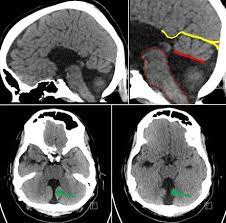

DWM is a complex constellation of findings, including VH/agenesis, cystic dilatation of the fourth ventricle, and an enlarged posterior fossa with upward displacement of the tentorium cerebelli and torcula herophili. Frequently, there are signs of hydrocephalus, with dilatation of the third and lateral ventricles . The terms “Dandy-Walker variant” or “Dandy-Walker complex” have been used to describe less severe forms of DWM, usually in cases when the posterior fossa is not enlarged, but the usage of these terms is discouraged because of their lack of specificity (Bosemani et al., 2015).

It may be difficult to distinguish DWM from other fluid collections causing upward rotation of the cerebellum. The measurement of the brainstem–vermian and brainstem–tentorium angles, which range from 4 to 17 and 21 to 44 degrees, respectively, may be helpful. Angles greater than 45 degrees suggest DWM (Volpe et al., 2012).